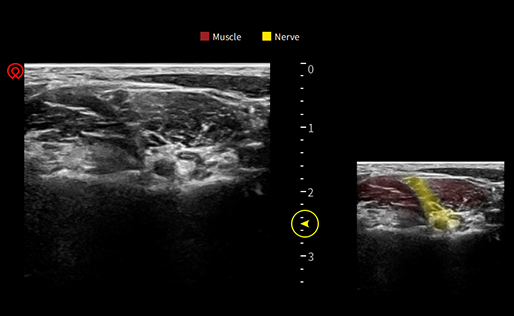

wiNerve

Интеллектуальное распознавание нервов с помощью искусственного интеллекта

Распознавание в реальном времени

Облачное решение

Поддержка нескольких нервов

Application pictures